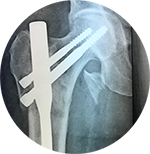

Other than the treatment for fractures he introduced spinal injury management in our region. He has done many knee joint and hip joint replacements. Because of that many old age arthritic patients are walking around without pain.

➤ Joint replacement